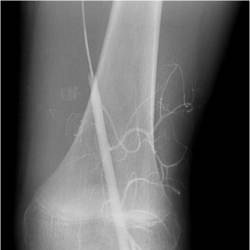

Gallery of Unlabled Radiographs from Lecture (Dr. French) - 2020

Click a thumbnail to enter the gallery display. Click the file name link at the bottom left of the gallery display to view the image at high resolution.

Labeled Plates from Lecture (Dr. French) - 2020

RadiologyLowerLimbThoraxQuestionPoolLabeled_01_2020.pdf

Click right side of plate to step forward or left side of plate to step backward.